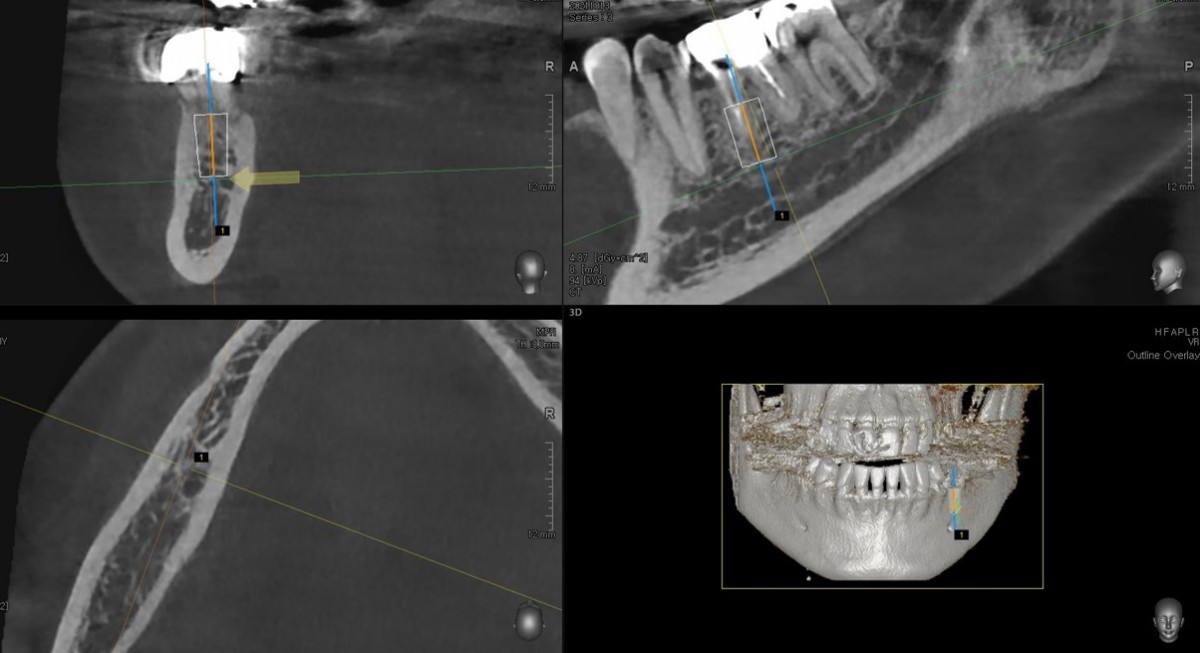

Immediate placement of an implant (Arum Dnetistry NB1, 5*8.5)

A 51-year-old patient complained of an

old-crowned molar. The lower left molar had a gold crown, and the margin showed discoloration indicative of inner caries. Also, it had furcation-involved periodontitis

with an apical lesion.

Extraction and immediate placement of an implant.

▲Arum Dentistry NB1 fixture (5*8.5mm)